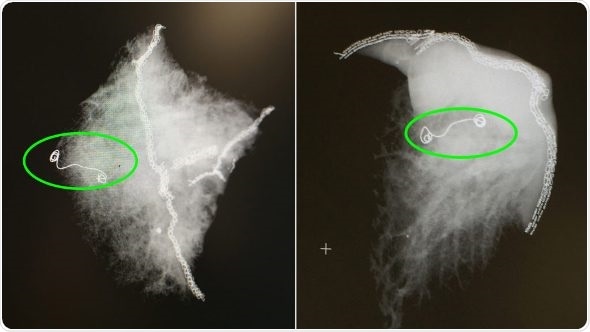

X-ray images of lung samples with the microcoil. (Courtesy: Cleveland Clinic)

Microcoil localization offered an alternative. The two-stage procedure typically proceeds in the following manner: after the patient goes to sleep in the operating room, a radiologist, using the hybrid operating room CT scanner and its advanced software capabilities, inserts a needle pre-loaded with a soft, fiber-coated platinum thread through the chest wall, then through the lung and finally, into the target nodule. This coil is carefully anchored to the nodule before the needle is removed.

Using video-assisted thoracoscopic technology (VATS), a thoracic surgeon locates the coil on the membrane around the lungs – the pleural surface – and carefully resects it along with the wedge of tissue containing the small nodule or lesion. The team can then instantly examine the tissue, make a diagnosis and, if necessary, perform further surgical treatment.